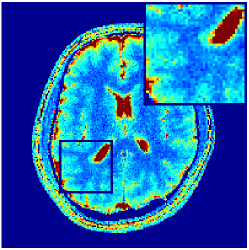

Two sets of experiments were conducted here: first, we used the 2D and 3D acquisition sequences for scanning a healthy volunteer’s brain (real-world acquisitions). Figures 6 and 7 display the parametric maps reconstructed from 2D spiral and radial readouts. We computed the T1, T2 and proton density (PD) maps using baseline reconstruction algorithms ZF, VS, LR, FLOR, AIR-MRF and our proposed LRTV. While baselines use DM either for quantitative inference or also during reconstruction (i.e. AIR-MRF), we further compare the DM-free LRTV’s performance when cascaded to DM, KM and MRFResnet for quantitative inference. For the 3D spiral acquisitions we compared LRTV and its closest competitor VS in Figure 8. Outcomes from other tested algorithm are displayed in the supplementary materials (Figure S5). Since FLOR does not use dimensionality-reduction, our system ran out of memory during 3D reconstruction; hence results are not reported in this case.

VI-E1 Discussion

The LRTV-DM and LRTV-MRFResnet perform on par, and both outperform all tested baselines for reconstructing T1, T2 and PD maps in all acquisition schemes. This can be observed both visually in Figures 6, 7, 8, S2 and S3, and quantitatively in Table IV across all tested metrics. Other baselines were unable to successfully remove the under-sampling artefacts in TSMIs, and these errors propagated to the parameter inference phase and resulted in inaccurate maps. Temporal-only priors incorporated within LR are shown insufficient to regularise the inverse problem and LR sometimes (e.g. 2D spiral acquisitions) can admit solutions with even stronger artefacts than the model-free ZF baseline. This issue was previously studied for other non-Cartesian MRF readouts that similar to our spiral/radial trajectories, miss to sample the corners of the k-space in all timeframes (see section 2.2.2 and figure 2 in [19]). In the absence of reference for the k-space corners information, the LR iterations despite minimising the objective can converge to solutions with high-frequency artefacts, as visible in the computed maps. This highlights the need for adding an appropriate spatial-domain regularisation. FLOR reduces the LR’s artefacts but this improvement is limited because the suggested nuclear norm penalty does not incorporate an explicit spatial regularisation. Further for reducing artefacts, FLOR can introduce an undesirable bias in the computed T1/T2 maps e.g. see error maps in Figures S2 and S3. The non model-based VS baseline incorporates spatial regularisation and results in spatially smoother maps than ZF and LR, but it is unable to output artefact-free images. Further and consistent with our in-vitro experiment, we observe that VS overestimates the T2 values (e.g. in White and Grey matter regions) in tested 2D acquisitions i.e. the spatial regularisation trades off agains the quantification accuracy. The model-based AIR-MRF adds spatial regularisation through 2D/3D low-pass Gaussian filters however this trades off the sharpness of the computed maps and can increase the errors at the tissue boundaries (we searched Gaussian spreads that keep the blurs and high-frequency artefacts minimal). For our acquisition readouts, Gaussian filters performed better than disk filters of [19] for avoiding strong Gibbs artefacts. On the other hand, the spatiotemporally regularised LRTV greatly improves the TSMI reconstructions i.e. 4 dB enhancement compared to the closest competitor baseline (Table IV). This enables computing accurate and aliased-free multi-parametric inference using DM or the DM-free learning-based alternative MRFResnet as visible in Figures 6, 7, 8, S2 and S3. MRResnet and DM score competitive quantitative inference results i.e. T1 and T2 MAPE less than 5% and 9%, respectively (Table IV). KM also outputs comparably accurate T1 maps, however this shallow learning model despite having a model size larger than MRFResnet, is unable to learn accurate T2/PD quantification and it results in poor estimated maps, consistent with our observations in section VI-C.